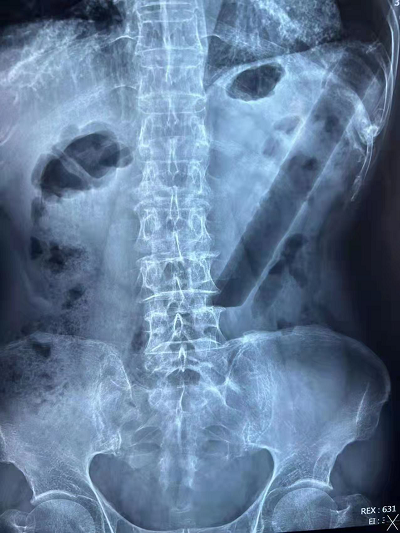

3月19日下午临近下班,肛肠二科门诊赵金龙医生接诊了一名85岁高龄的特殊患者,患者在外院行腹部平片,示结肠异物。经过详细询问病史后得知患者两天前因排便不畅,自行用一根直径约3cm,长约20cm的空心硬塑料管协助通便,结果无法自行取出。随着时间的推移,塑料管的位置也越来越深,患者下腹部也开始胀痛不适,辗转市内其他医院后来到我院肛肠二科门诊就诊。

赵医生在向韩义民主任汇报患者病情后将患者收住入院,完善相关检查后紧急在结肠镜下行“经内镜异物取出术”。结肠镜显示异物嵌顿于乙状结肠距肛门口约25cm的位置,直肠和乙状结肠多发片状溃疡。因为异物为比较锐利的斜切口,所以取出时一不小心就会划破肠道黏膜,甚至会造成肠穿孔,所以整个操作过程需要高度的警惕和完美的配合。在缪磊、赵金龙、张祚纶三位医生和谭晓霞护士相互配合下,沿着肠道的走形方向缓慢退镜,直至将异物拖至直肠,然后借助器械和外力的作用将异物挤压变形,最后将异物拖出直肠,整个手术过程历时1个小时。术后给予消炎等支持对症治疗,患者于3月23日痊愈出院。